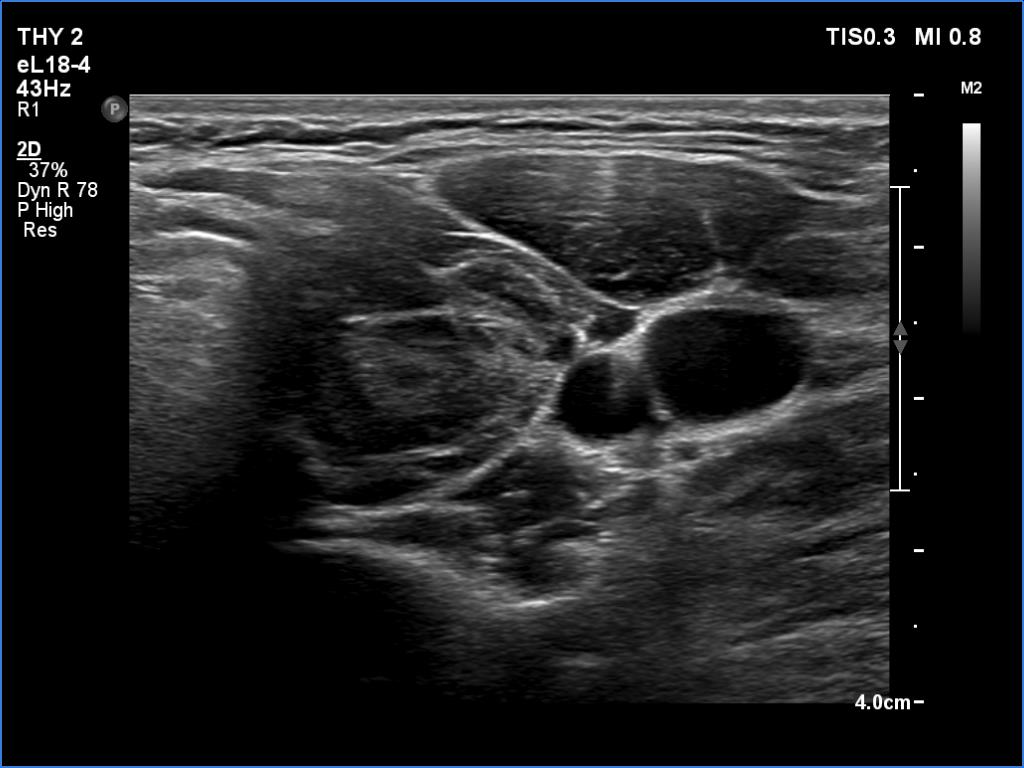

Ultrasonography. The thyroid was echonormal and had hypoechoic areas. The echogenicity index exceeded 50%. The pattern did not correspond to nodule. The vascularity was not specific.

Compared with the previous examinations, the ultrasound pattern remained unchanged.

Comment. This is the most common presentation of Hashimoto's thyroiditis, unfortunately not infrequently misinterpreted as a multinodular goiter. The multiplicity and the irregular borders of the discrete lesions are the main clues to avoid misinterpretation of these lesions as nodules.